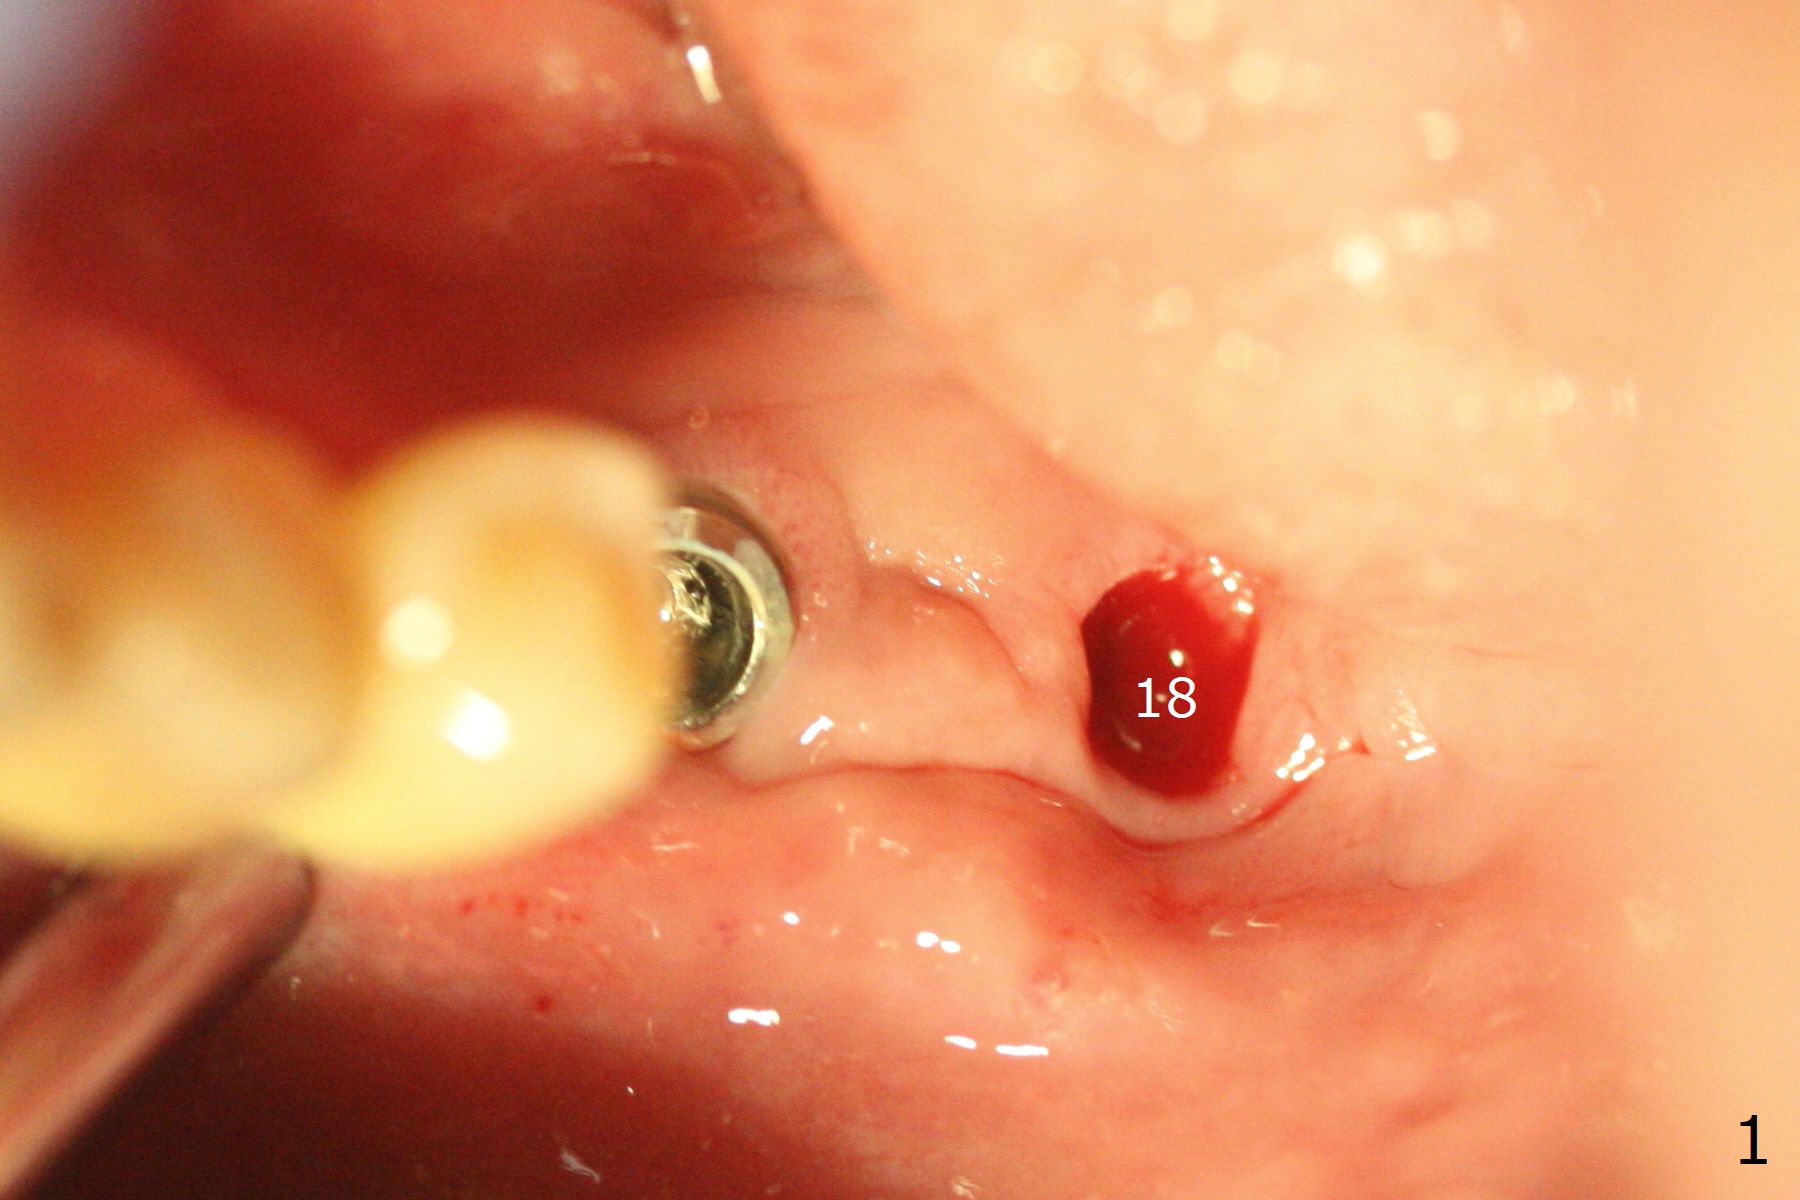

While the implant at #18 is easily removed, the one at #19 is superficial with buccal nonkeratinized gingiva (Fig.1). The latter is removed. Two small pieces of onlay graft is harvested from the left ramus and fixed in the defects with pins (Fig.2), surrounded by allograft with PRF. Since the pin at #18 looks violating the Inferior Alveolar Canal (Fig.2 C), CT is taken. In fact the pin perforates the lingual plate at #18 (Fig.4, as compared to Fig.3 (#19)). It leaves in place. Postop the wound dehisces with loss of allograft and exposure of the screws. The wound heals gradually mesiodistal with exposure of #18 screw 2.5 months postop. Follow up is disrupted by coronavirus pandemic.

It appears that short implants could be placed mesial to the original sites (Fig.5,6), 5x6 and 5x5 mm at #19 and 18, respectively, with guide as lingual as possible. The exposed buccal threads will be covered by 3-D Bond (Fig.9 white line, post decortication (red)), collagen plug and PGA suture. Healing screws are most likely used, although healing abutments should be prepared if they help wound closure.